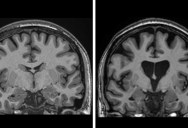

During the surgery – a pioneering type of gene therapy which targets the huntingtin gene in the DNA – a safe virus is infused into the brain.

This virus delivers tiny DNA into brain cells, which then learn to replicate the gene-silencing DNA sequence, meaning that levels of huntingtin in the brain will be reduced, and its brain cell killing properties disabled.